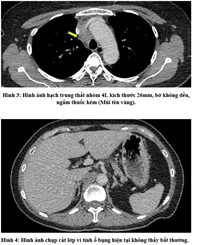

Ung thư thận là loại ung thư thường gặp đứng thứ 14 trên toàn cầu, với hơn 430.000 ca mới được chẩn đoán vào năm 2020, và 434840 ca mắc trên toàn cầu vào năm 2022. Tỷ lệ mắc thay đổi theo khu vực địa lý, cao hơn ở châu Âu và Bắc Mỹ. Ung...